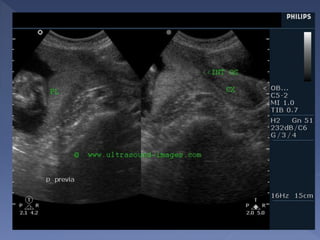

 Anterior/Posterior/Lateral/Fundal

 Placenta Previa

› Marginal

› Partial

› Complete

 Low-Lying

 Inner border of placenta against the uterine wall

has the combined hypoechoic myometrium and

interposed basilar layer = hypoechoic band called

the decidua basalis (contains maternal blood

vessels)

 Outer surface abutting the amniotic fluid =

chorionic plate (chorioamniotic membrane)

= bright specular reflector

 Placental thickness judged subjectively

But if measure at mid position or cord insertion 2-4 cm

= normal

Placental calcification. Scan of posterior placenta at 39 wks

shows calcification along the basal plate (arrows), chorionic

plate (open arrows), and septa (arrowheads

Midline sagittal scan at 28 weeks shows the posterior

placenta (P) completely covering the cervix (C). B,

maternal bladder

the placenta had invaded

through the myometrium to

the bladder wall